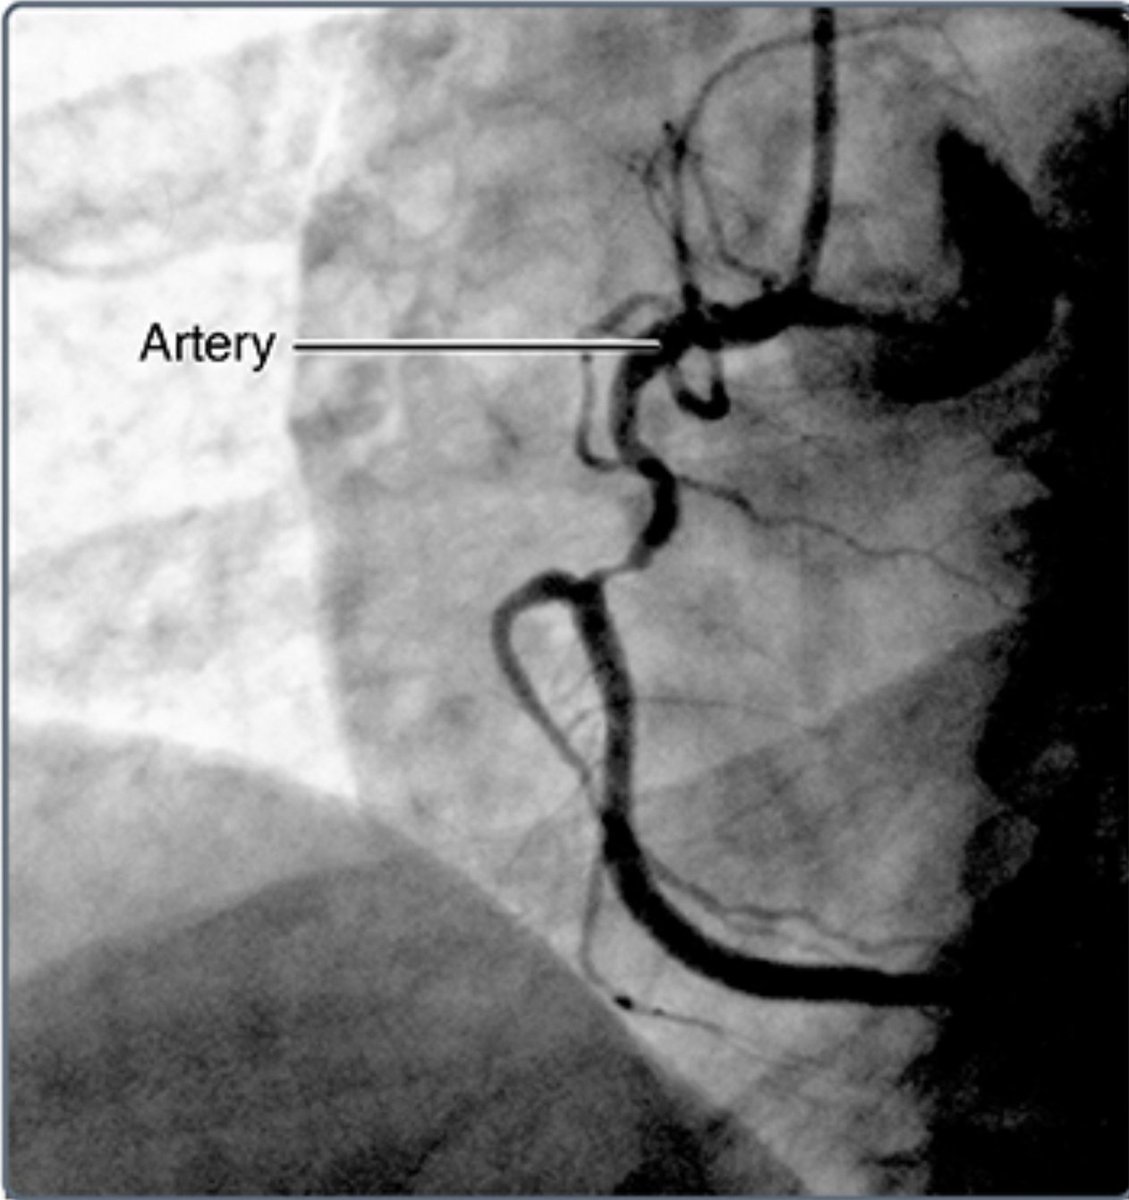

حيث يتم إدخال القسطرة (أنبوب رفيع طويل) في الشريان أو الوريد في منطقة العانة، أو العنق، أو الذراع ويتم ايصاله للقلب عبر الأوعية الدموية المتصلة بالقلب.

* تحديد موقع تضيُّق أو انسِداد الأوعية الدموية التي قد تُسبِّب ألمًا في الصدر.

يتم إجراء قسطرة القلب في مختبر القسطرة وهي منطقة معقمة من خلال أجهزة خاصة للأشعة السينية.